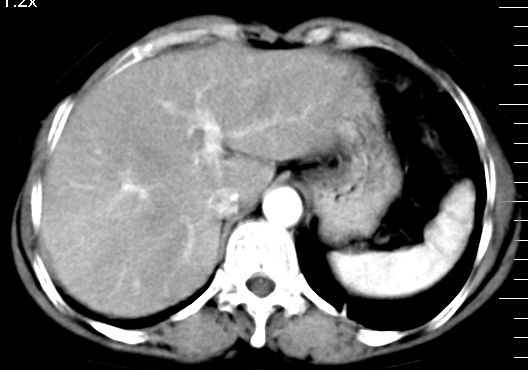

ct表现:

肝大小形态未见异常,肝内外胆管无扩张,肝s8段见一动脉期明显血管样强化结节,门脉期呈高密度,延迟期呈等密度,胆囊不大,增强扫描见胆囊及胆囊颈管壁增厚,有强化。

双肾灌注良好,代谢增快,动脉期肾盂见造影剂,左肾下极背侧见一略低密度病灶,延迟期见似不强化囊肿,双侧肾上腺未见异常。

胰腺及脾未见异常。肾门水平腹膜后见小淋巴结。腹腔未见积液征象。

1、胆囊炎(轻度)。

2、肝s8段结节,考虑小血管瘤。

3、左肾下极低密度灶,考虑囊肿可能性大,建议随访,除外小肾癌(无强化可以基本除外)。

4、目前ct表现尚不能解释患者上腹部疼痛,建议上消造影检查,除外胃炎等疾患。